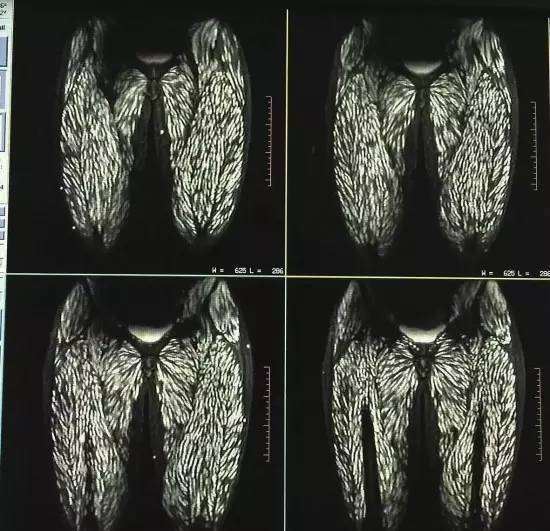

Thật bất ngờ, kết quả xét nghiệm X-quang đã khiến tất cả các nhân viên y tế bị sốc, thậm chí ngay cả đến các bác sĩ đầu ngành lâu năm trong nghề cũng phải ngạc nhiên và giật mình vì kết quả khủng khiếp này. Hoá ra từ màn hình chụp X-quang cho thấy phần sau nhãn cầu, phần đùi, bụng và cơ lưng cùng nhiều nơi khác trên thân thể cô đều bị bao phủ bởi ký sinh trùng. Ngay cả đến lưỡi, phần da mặt đều bị lây nhiễm đến. Sau khi có kết quả kiểm tra máu bác sĩ khẳng định Đình Đình dương tính với sán kháng thể, vì vậy cô đã bị nhiễm bệnh giun sán nặng.

Trên màn hình cho thấy thân thể cô bị bao phủ với những đốm trắng, đó chính là những ký sinh trùng.

Do cô đã có cả quá trình thời gian dài ăn thịt lợn sống kiểu đó nên các bác sĩ còn phát hiện thêm giun sán đã đi sâu vào não và khiến xuất hiện hiện tượng vôi hoá. Điều đó chỉ ra rằng có giun sán chết trong đó. Hơn nữa mắt người bệnh còn bị lồi lên, xuất huyết võng mạc, toàn thân bị nhiễm trùng nhiều nơi, đôi khi kèm theo co giật, tình trạng nghiêm trọng như vậy đến các bác sĩ cũng lần đầu tiên gặp phải.